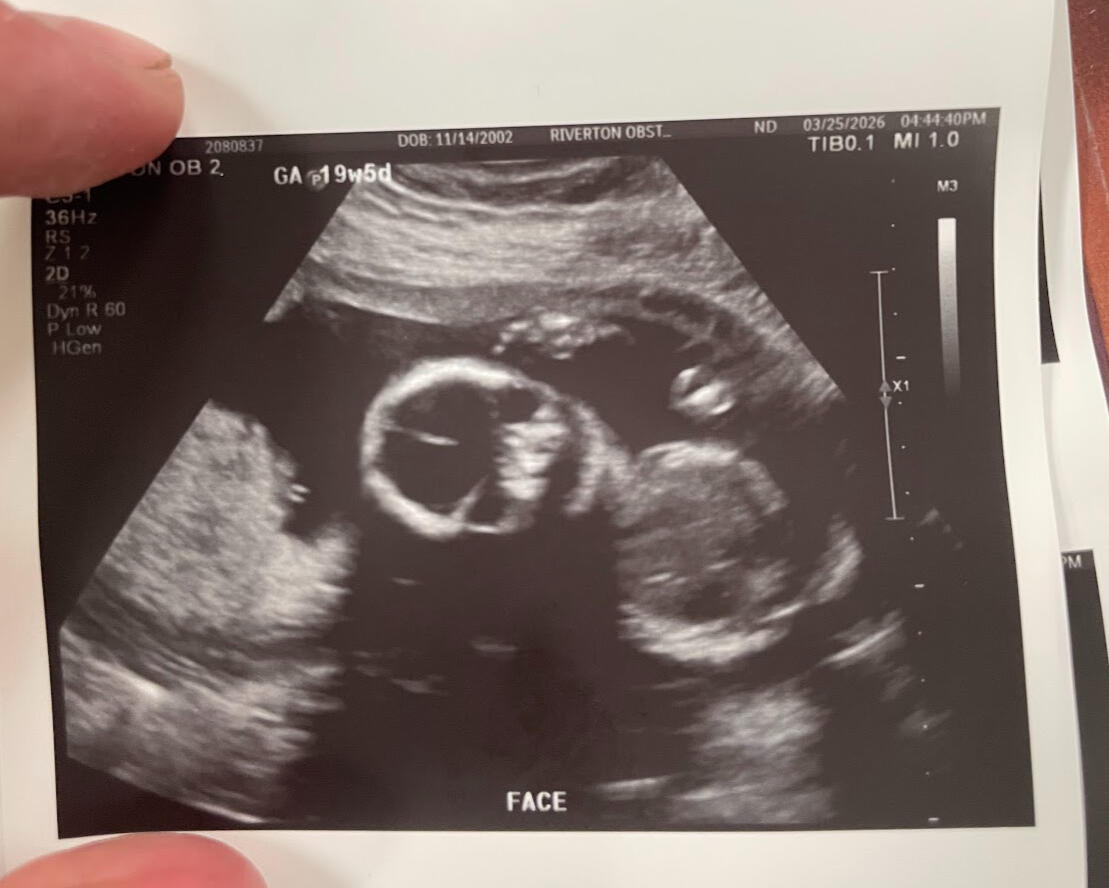

Ultra sound @ March 25th

It has only been three months and three weeks since we found out we are having a child.Since then, we have gained a bassinet in our bedroom and a closet filled with new baby clothing. New artwork for our nursery and overall has been the subject of conversation every single day since.It is sufficient to say that our lives have changed forever.Having this drastic a change in such a short time has come with much stress and complications, and almost all aspects of our lives.Most surprising are the emotional changes we have undergone over the past three months. As it turns out, (from parenting books and colleagues’) husbands and wives will go through drastic hormonal changes while the wife is pregnant.All this has led to a lot of planning for our future baby. There are times when I feel more stress than I've ever felt in my entire life.However, in the same breath, I believe I have also felt the most gratitude and love for my family that I have ever felt.For sure, things are differentBut overall, despite all the sleepless nights and worrying about our baby’s future, I’ve been able to see the world in a different, more positive light than ever before.Abree and I have been dreaming of this moment and have been planning for our new child. Now that it is here, it feels almost surrealWe are very excited